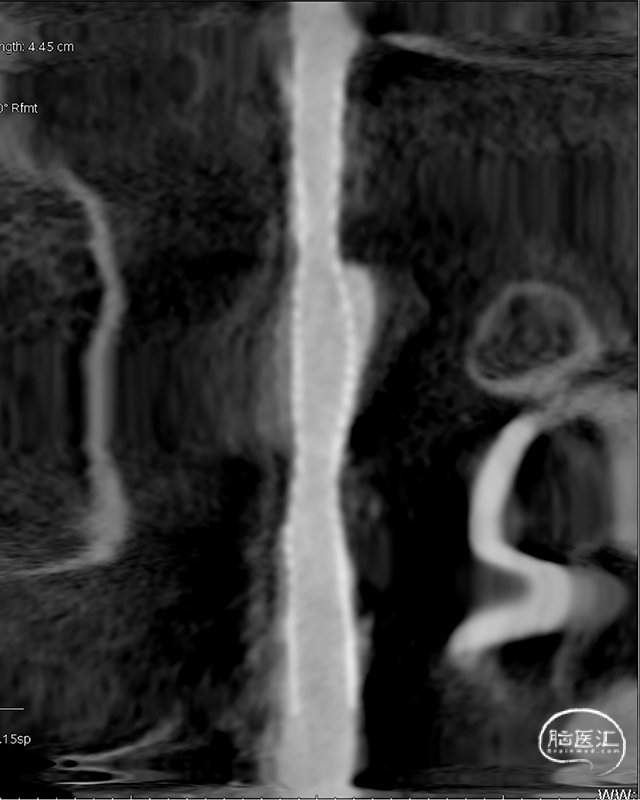

DSA示双侧椎动脉V4段狭窄,右侧为著且合并梭形动脉瘤。

术前DSA。